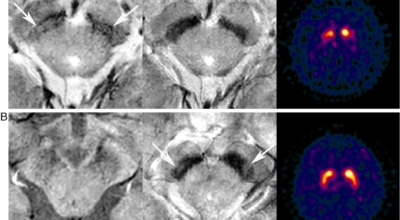

파킨슨병은 도파민 분비 신경 세포의 소실로 발생하는 질환으로 알려져 있는데요 도파민이란 뇌의 신경세포에서 만들어지는 물질로 세포와 세포 간의 신호를 전달하는데 이용되는 신경 전달 물질 중 한가지로 이 도파민이 감소함에 따라 파킨슨병이 걸린다고 하는데 이 도파민 세포가 떨어지는 이유는 아직 정확히 밝혀지지 않았다고 합니다.